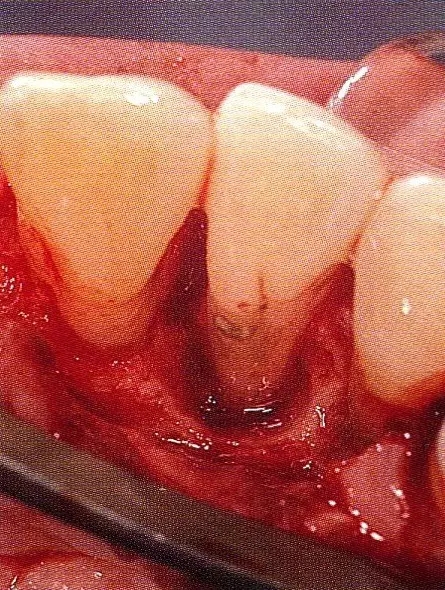

案例3   針對(duì)3壁性垂直性骨缺損使用非吸收性膜進(jìn)行再生治療,再翻瓣時(shí)進(jìn)行骨形態(tài)修整的病例。

▲圖7-1  左下6近中可觀察到3壁性垂直性骨缺損。此病例考慮到齦瓣供血關(guān)系,在前磨牙部位進(jìn)行了減張切開,沒有進(jìn)行縱切開。并利用刮治器、牙周外科用車針進(jìn)行了徹底的骨缺損部位搔刮。